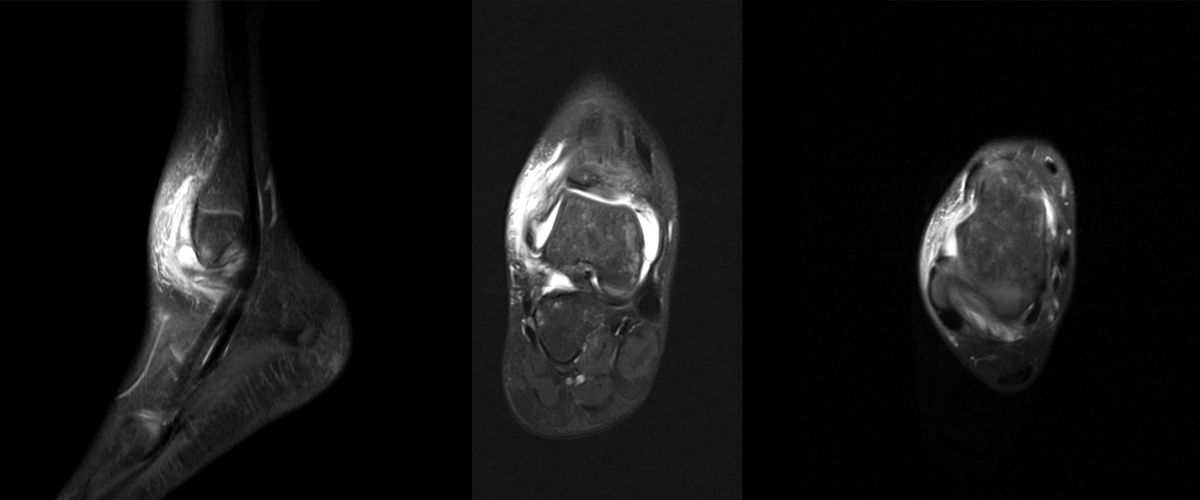

MRT

Die Kernspintomographie hat ihre Stärke in der Darstellung von Weichteilverletzungen. Insbesondere Verletzungen der Wachstumsfuge, des Periosts und der Bänder lassen sich gut visualisieren. Nachteilig ist die Untersuchungsdauer von 20-30 Minuten. Bleibt das Kind während dieser Zeit nicht ruhig liegen, kommt es zu Bewegungsartefakten, welche die Beurteilbarkeit der Bilder beeinträchtigen.

Os subfibulare

Multiple laminäre Ausrisse des fibularen Bandapparats aus der Fibulaspitze können zur Entwicklung eines Os subfibulare führen. Das Os subfibulare findet sich unterhalb der Fibulaspitze ventral der Peronealsehnen. Ohne Schmerzsymptomatik bzw. Aktivierung im MRT hat Das Os subfibulare keinen Krankheitswert. Ein mobiles Os subfibulare führt zu einer lokalen mechanischen Reizung teilweise in Verbindung mit einer Instabilität des Sprunggelenks. Im MRT zeigt sich eine Aktivierung des instabilen Areals. Bei anhaltenden Schmerzen besteht die Behandlung in einer operativen Entfernung des Knochens mit Refixation des Kapselbandapparats.

Os trigonum

Das Os trigonum lässt sich als isolierter Knochen dorsal des Talus seitlichen Röntgenbild darstellen. Normalerweise hat das Os trigonum keine klinische Relevanz. Bei entsprechenden Beschwerden und einer Aktivierung im MRT kann der Knochen arthroskopisch entfernt werden. Gehäuft beobachten wir eine mechanische Problematik durch das Os trigonum bei jugendlichen Fußballspielern und Tänzerinnen.

Osteochondrale Verletzungen

Osteochondrale Verletzungen können infolge eines Distorsionstraumas beobachtet werden (Taluskantenfraktur), teilweise lässt sich auch kein Trauma eruieren. Der es sich bei osteochondralen Verletzungen um keine Arthrose handelt, ist gerade bei Schmerzfreiheit ein defensives Vorgehen angezeigt. Bei offenen Wachstumsfugen kann eine osteochondrale Verletzung unter konservativer Therapie ausheilen.

Eine retrograde Anbohrung ist indiziert, wenn sich im MRT Verlauf eine zunehmende Sklerosierung im Randbereich der Läsion zeigt bei intakter Knorpeloberfläche.

Instabile Knorpelareale werden arthroskopisch entfernt in Verbindung mit einer Mikrofrakturierung der subchondralen Knochenlamelle.